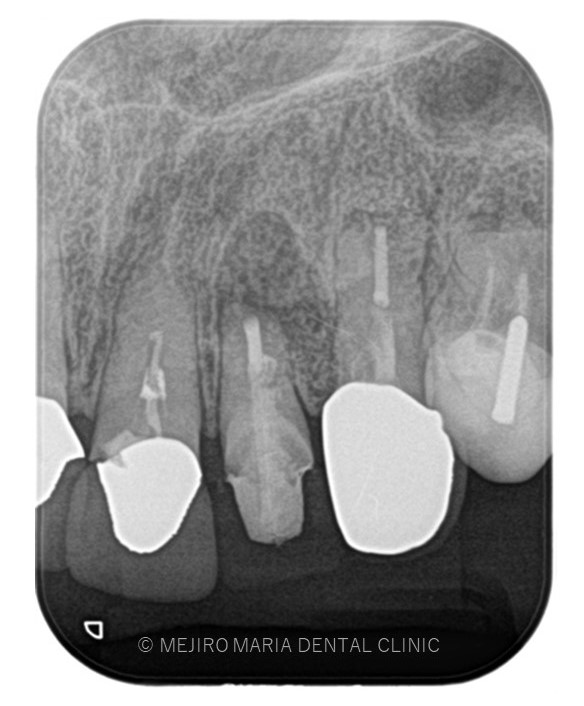

でのリカバリー_治療前感染した人工骨が確認できるレントゲン画像.jpg)

でのリカバリー_治療前、感染した人工骨部分レントゲン画像.jpg)

今回の症例は、他院にて歯根端切除術を行った根尖部(歯の根の先)に充填された人工骨の感染が原因と考えられます。